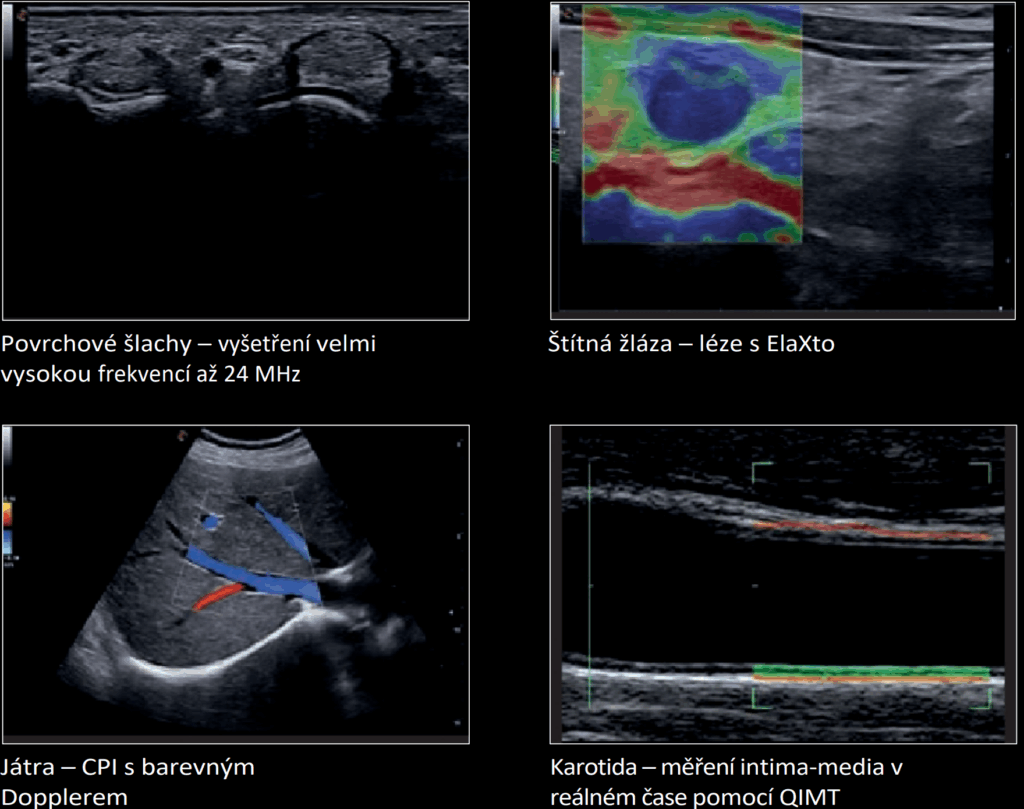

Široké portfolio sond

Sondy Esaote iQProbes splňují nejvyšší standardy kvality a využívají nejmodernější technologie pro širokou škálu klinických aplikací.